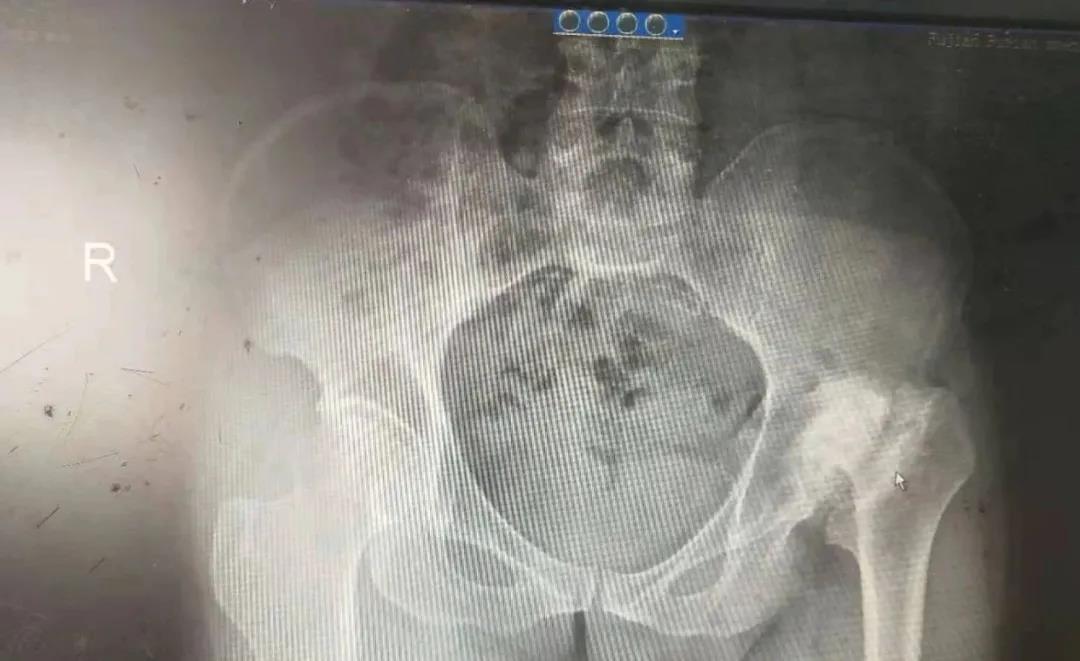

聽聞原解放軍九五醫(yī)院骨科主任林國兵加盟盛興醫(yī)院任業(yè)務(wù)副院長,家屬遂帶其前來就診,拍片檢查發(fā)現(xiàn)患者左側(cè)髖關(guān)節(jié)脫位,股骨頭壞死,股骨頭被磨損的所剩無幾了,且已形成假關(guān)節(jié),左髖關(guān)節(jié)幾乎無活動度了,左下肢竟然較右側(cè)短縮10cm。經(jīng)林國兵仔副院長細(xì)查體、詢問病史后,初診斷左側(cè)髖關(guān)節(jié)病伴髖關(guān)節(jié)脫位及股骨頭壞死,并收住入院,準(zhǔn)備為其行左側(cè)人工全髖關(guān)節(jié)置換術(shù)。

術(shù)前